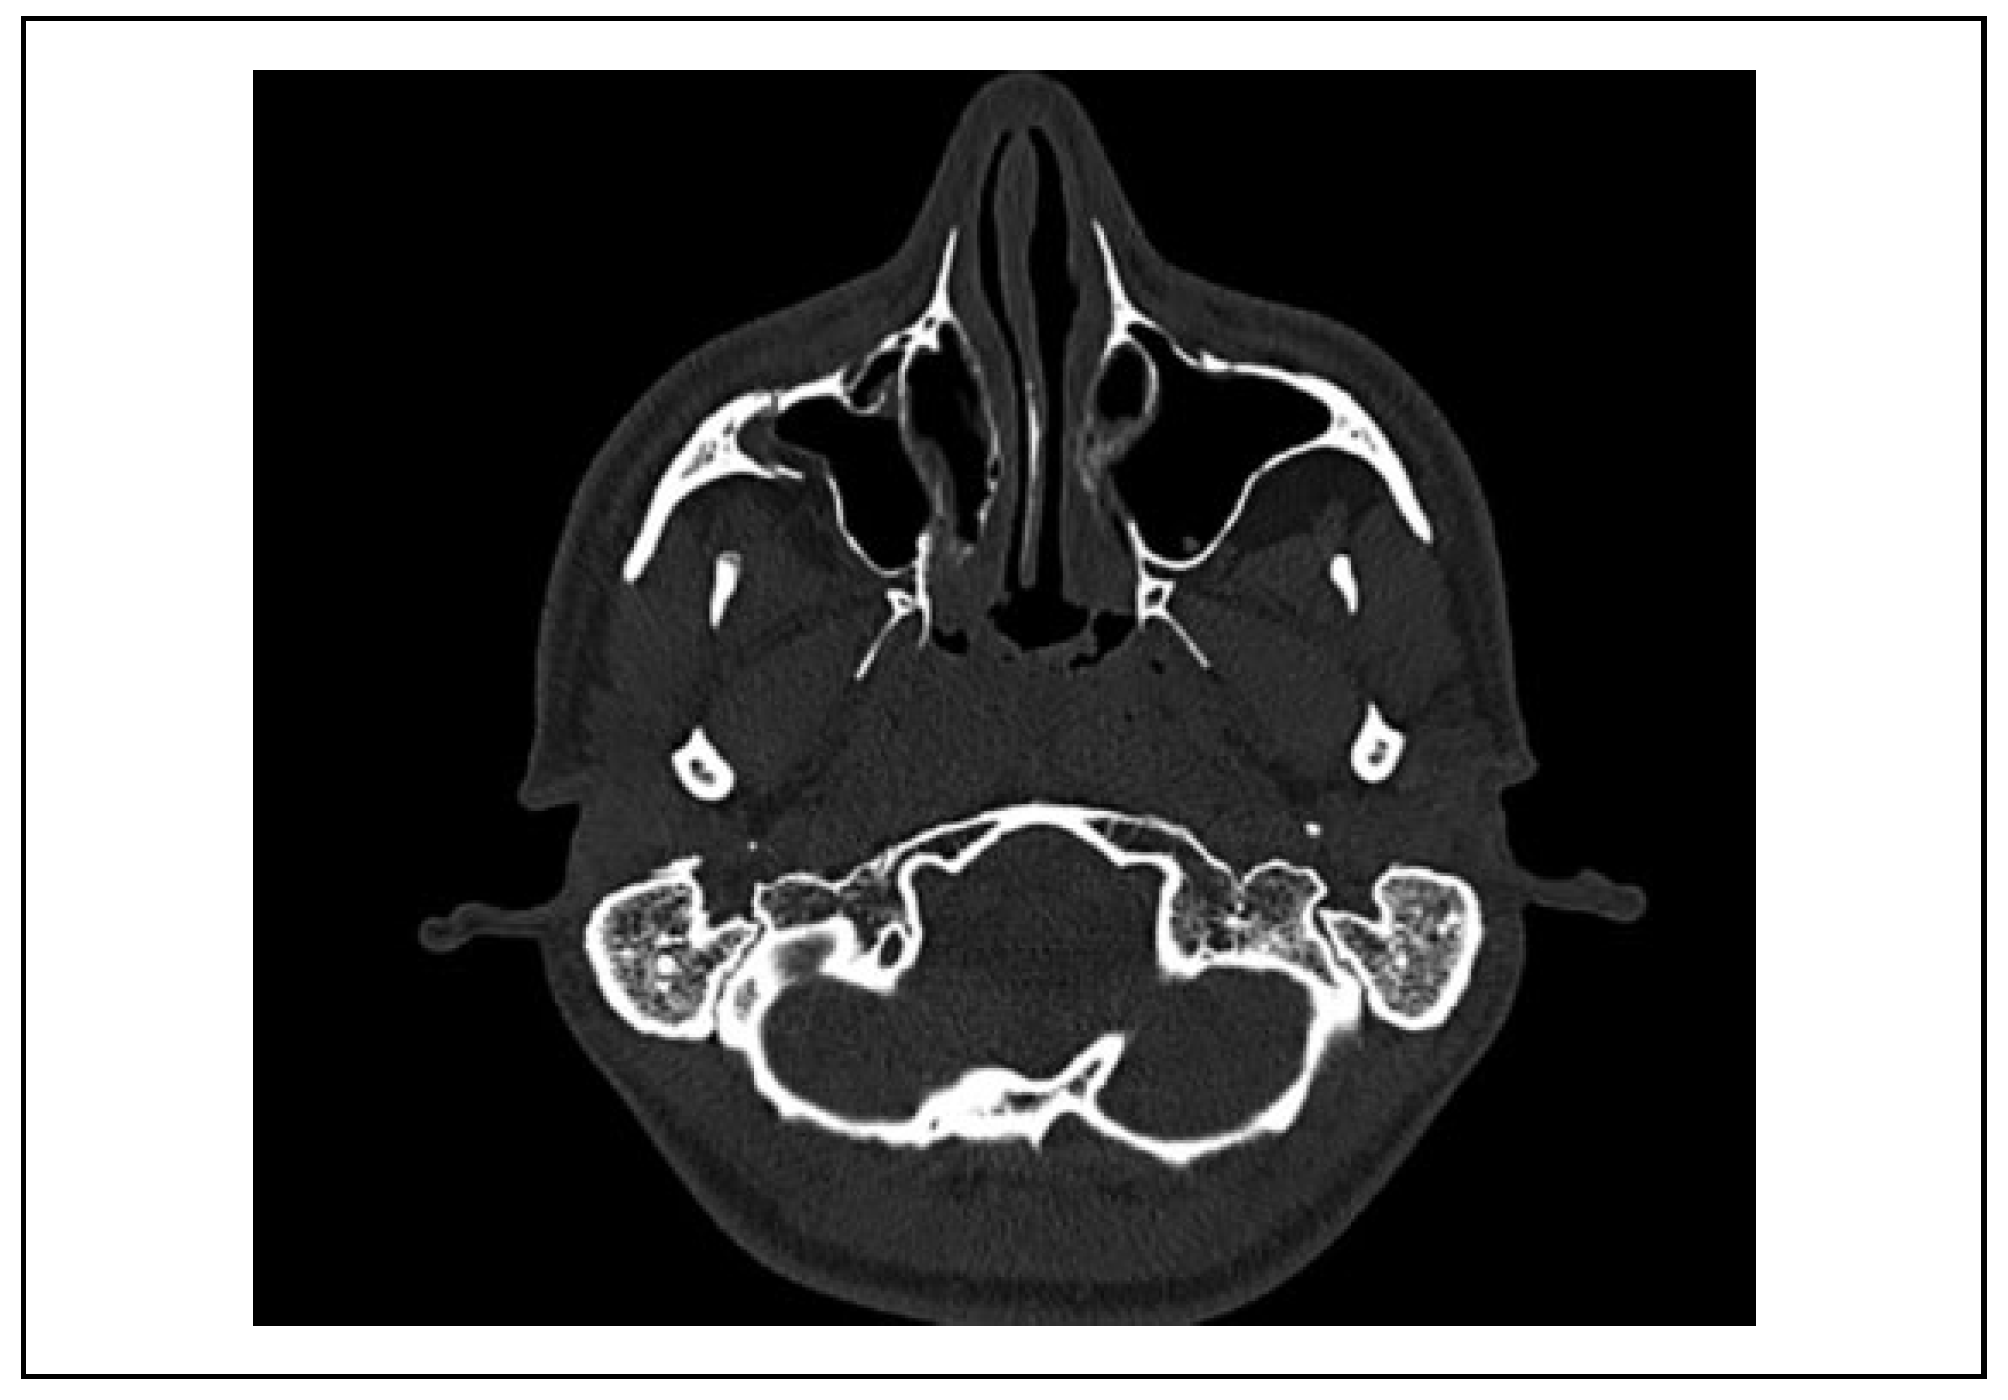

Case 1